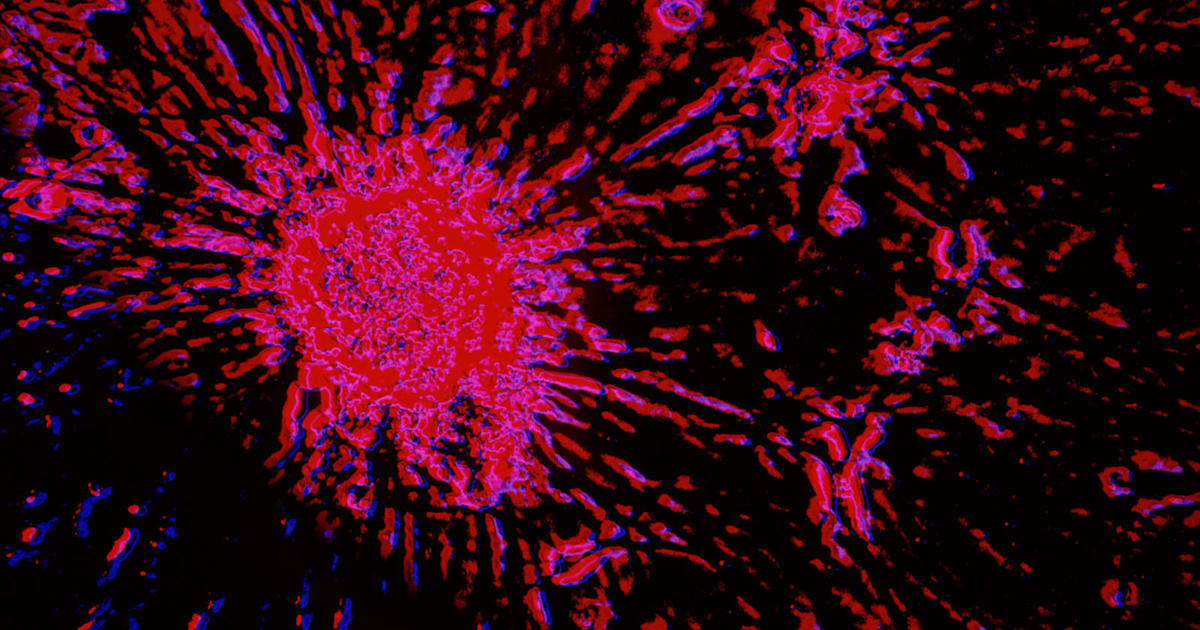

Cancer consumes fat to feed its metastatic march in mice